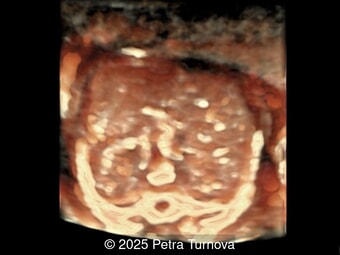

A 35-year-old secundigravida was referred to our unit at 20 weeks gestation for evaluation of suspected fetal skeletal abnormalities. Her first child was healthy, and her personal and family history were otherwise unremarkable. Two years later in a subsequent pregnancy, the patient presented for ultrasound evaluation. This examination was performed at 13 weeks of gestation and demonstrated the following findings: